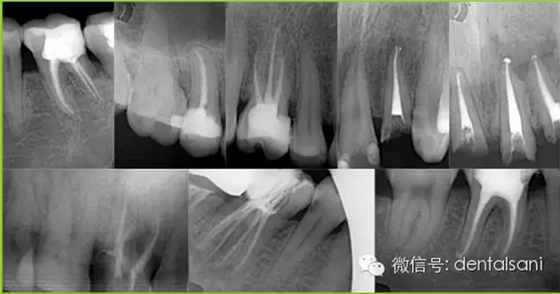

根管治療簡(jiǎn)單的說(shuō)就是通過(guò)根管的方式對(duì)于牙髓進(jìn)行一系列的治療,那么,現(xiàn)在根管治療已經(jīng)在口腔治療之中起到了非常重要的作用,一般是和補(bǔ)牙結(jié)合使用的,在整個(gè)根管治療過(guò)程之中需要注意什么呢?

適應(yīng)癥要選擇恰當(dāng)。根據(jù)病情,牙周狀況、X線片,病人的身體狀況等各方面因素來(lái)選擇,避免治療失敗。

4. 開髓時(shí)要參照X線片,鉆針不宜進(jìn)入髓腔太深,以免損傷和磨穿髓底。如果底損傷后,則難以尋找根管口,有條件者用根管口擴(kuò)大器。萬(wàn)一髓底磨穿,可以用丁香油氧化鋅暫封穿底處后(穿底大,應(yīng)先用雙氧水、生理鹽水輕輕沖洗),再繼續(xù)擴(kuò)管。待炎癥消除后,再用磷酸鋅或銀汞合金將底充好,根管治療應(yīng)繼續(xù)進(jìn)行。另外,凡是別人治療過(guò)的、開過(guò)髓的牙齒,接手之后必先拍X線片,因?yàn)橛袝r(shí)已經(jīng)穿底。